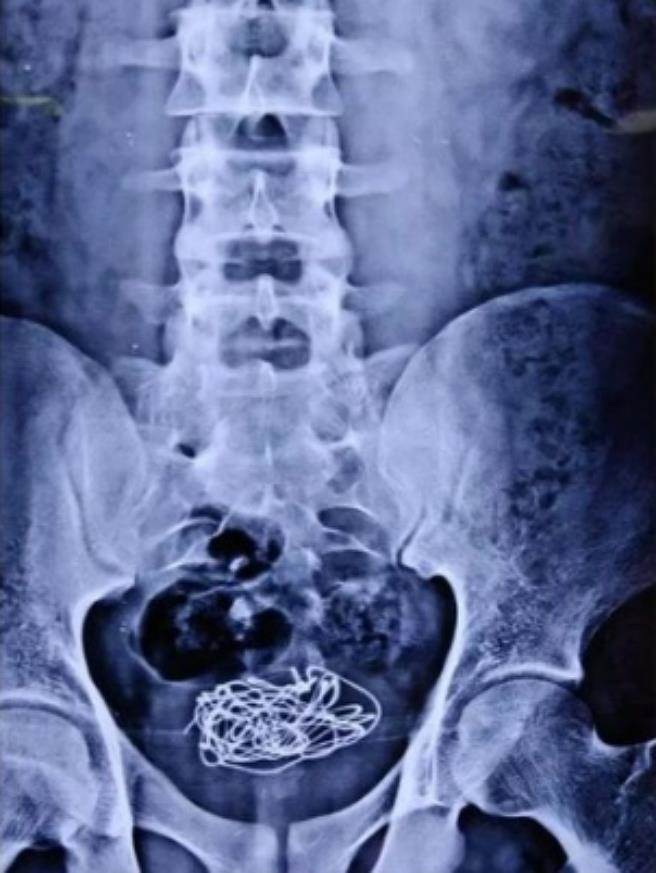

x光下可以看见少年膀胱内异物,图来自bmj.